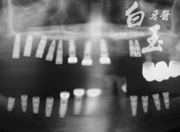

植入植體

治療中